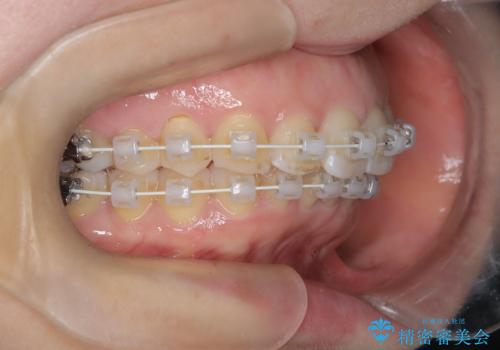

審美装置を用いたワイヤー矯正|非抜歯で歯の凸凹を改善

- 患者様は**歯の凸凹(叢生)**を気にされて来院されました。診査の結果、歯列のスペースが不足しているものの、抜歯をせずに改善できる状態でした。そこで、目立ちにくい審美装置(白いブラケットとホワイトワイヤー)を使用したワイヤー矯正を提案しました。歯列のアーチを広げながら、適宜IPR(歯の幅をわずかに調整する処置)を行い、非抜歯で自然な歯並びへと導く計画を立てました。

治療では、白いブラケットとホワイトワイヤーを使用し、矯正装置が目立ちにくいよう配慮しました。歯列を拡大しながら適切に歯を移動させ、IPRを併用することで、無理なくスペースを確保しました。見た目に配慮しながら、歯の凸凹をスムーズに整え、噛み合わせも改善。患者様からは「装置が思ったより目立たず、歯並びがきれいになって嬉しい」との声をいただきました。